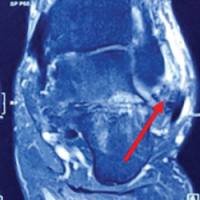

Following loose body removal, a partial synovectomy was performed, targeting areas of hypertrophic synovium while preserving healthy synovial tissue. Before reduction, femoral head vascularity was confirmed through drilling with a Kirschner wire, which demonstrated adequate bleeding, confirming preservation of vascular supply. Histopathological examination revealed nodular architecture typical of synovial chondromatosis (Fig. 4).

Figure 4: Histological picture with hematoxylin and eosin staining.

Each nodule consisted of hyaline cartilage with increased cellularity, clustered chondrocytes, and predominantly pyknotic nuclei. No mitotic figures were identified, confirming the benign nature of the lesion. The immediate posto-perative course was uncomplicated. The patient was mobilized with protected weight-bearing for 6 weeks, followed by progressive rehabilitation. At 3 months postoperatively, the patient had returned to full activities of daily living without pain or functional limitation. At 24-month follow-up, radiographic evaluation showed no evidence of femoral head avascular necrosis, disease recurrence, or progression of degenerative changes (Fig. 5). Clinical examination demonstrated full range of motion in all planes without pain or functional restriction (Fig. 6).